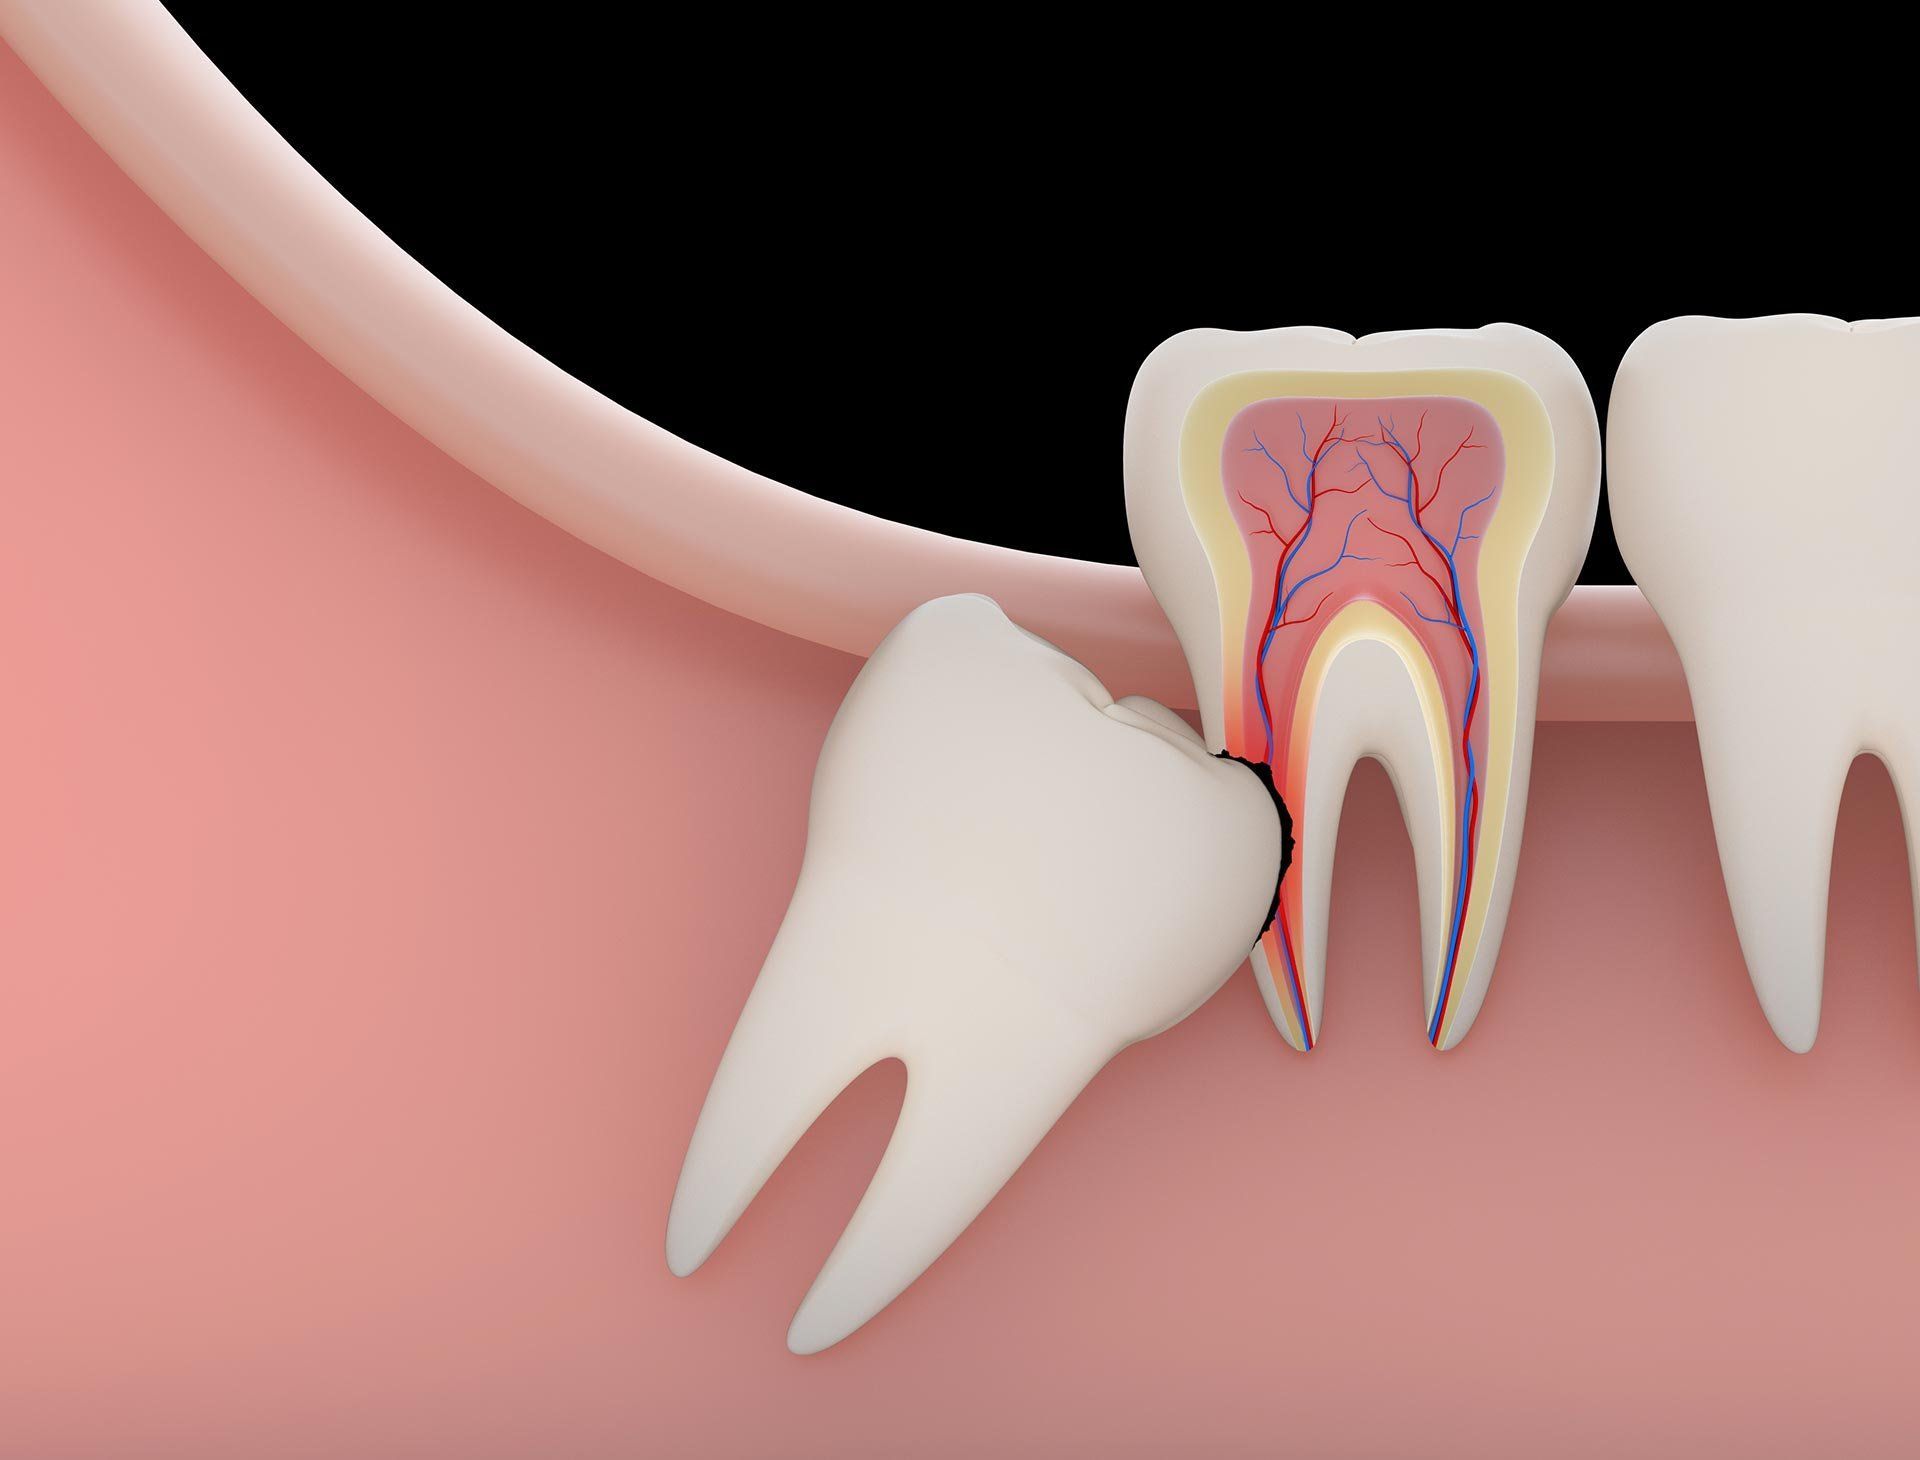

Surgical Wisdom Tooth Removal

Extract impacted or partially erupted wisdom teeth that are trapped under gums or bone. Advanced surgical techniques for complex cases.

Pressure Pain: When a wisdom tooth develops, it can cause a lot of pressure against the other teeth in the mouth as they try to make room. This can cause severe pressure pain, and can even lead to erosion of the other teeth.

Cyst Formation: A cyst (fluid-filled sac) can form from the tissue surrounding an impacted wisdom tooth. This can lead to bone destruction, jaw enlargement and movement or decay of nearby teeth. The removal of the tooth and cyst is required to avoid further bone loss. Tumors can develop inside these cysts, and they can even result in a fractured jaw if left to grow.

- If your wisdom tooth is still under the gums, growing in horizontally rather than vertically, this can put a lot of pressure on the surrounding teeth, leading to crowded and crooked teeth. This can also occur when there is not enough space in the jawbone or mouth to accommodate the wisdom tooth. You may require braces to repair the damage.